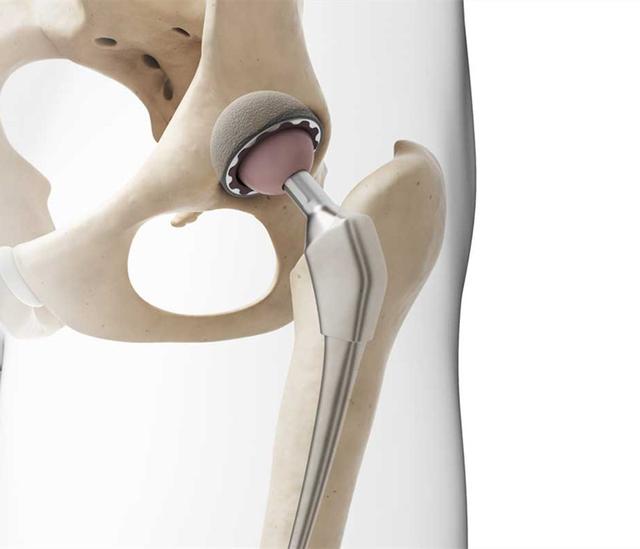

• 髋关节置换后,还能跑步吗,该注意哪些问题?

在髋关节置换手术中,受损的软骨和骨头被移除,并用金属、塑料或陶瓷假体替换。医生还可能会使用水泥将人工关节固定到骨头上。过大的冲击会增加股骨干断裂和假体松动的风险,并加速假体部件表面的磨损。传统上不建议患者康复后跑步。实际上并不绝对,主要取决于骨骼质量,假体材料,手术范围以及患者的整体健康状况。如果打算跑步,必须提前与医生讨论,如果可行,询问医生如何安全地恢复跑步。以下为一些建议:结合步行和慢跑在身